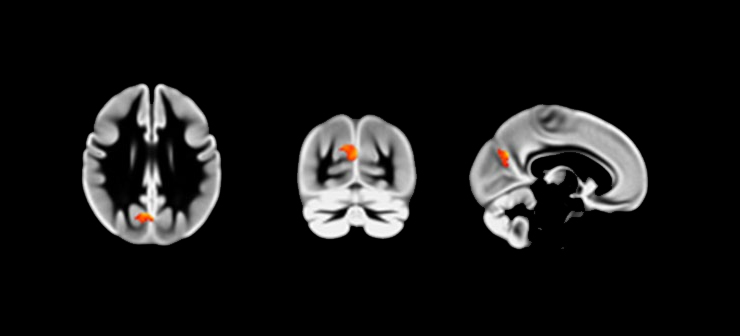

Region of greater precuneus grey matter volume

“What we found was that evening types had greater grey matter volume in an area of the brain called the precuneus,” said Dr Norbury, an avowed morning person.

“We know from meta-analysis and previous work that this is a key component of our social brain. We also know that reduced volume in this area has been associated with empathy, agreeableness and cooperation, so it ties nicely with behavioural data that suggests early chronotypes tend to engage in more pro-social behaviours than evening types.